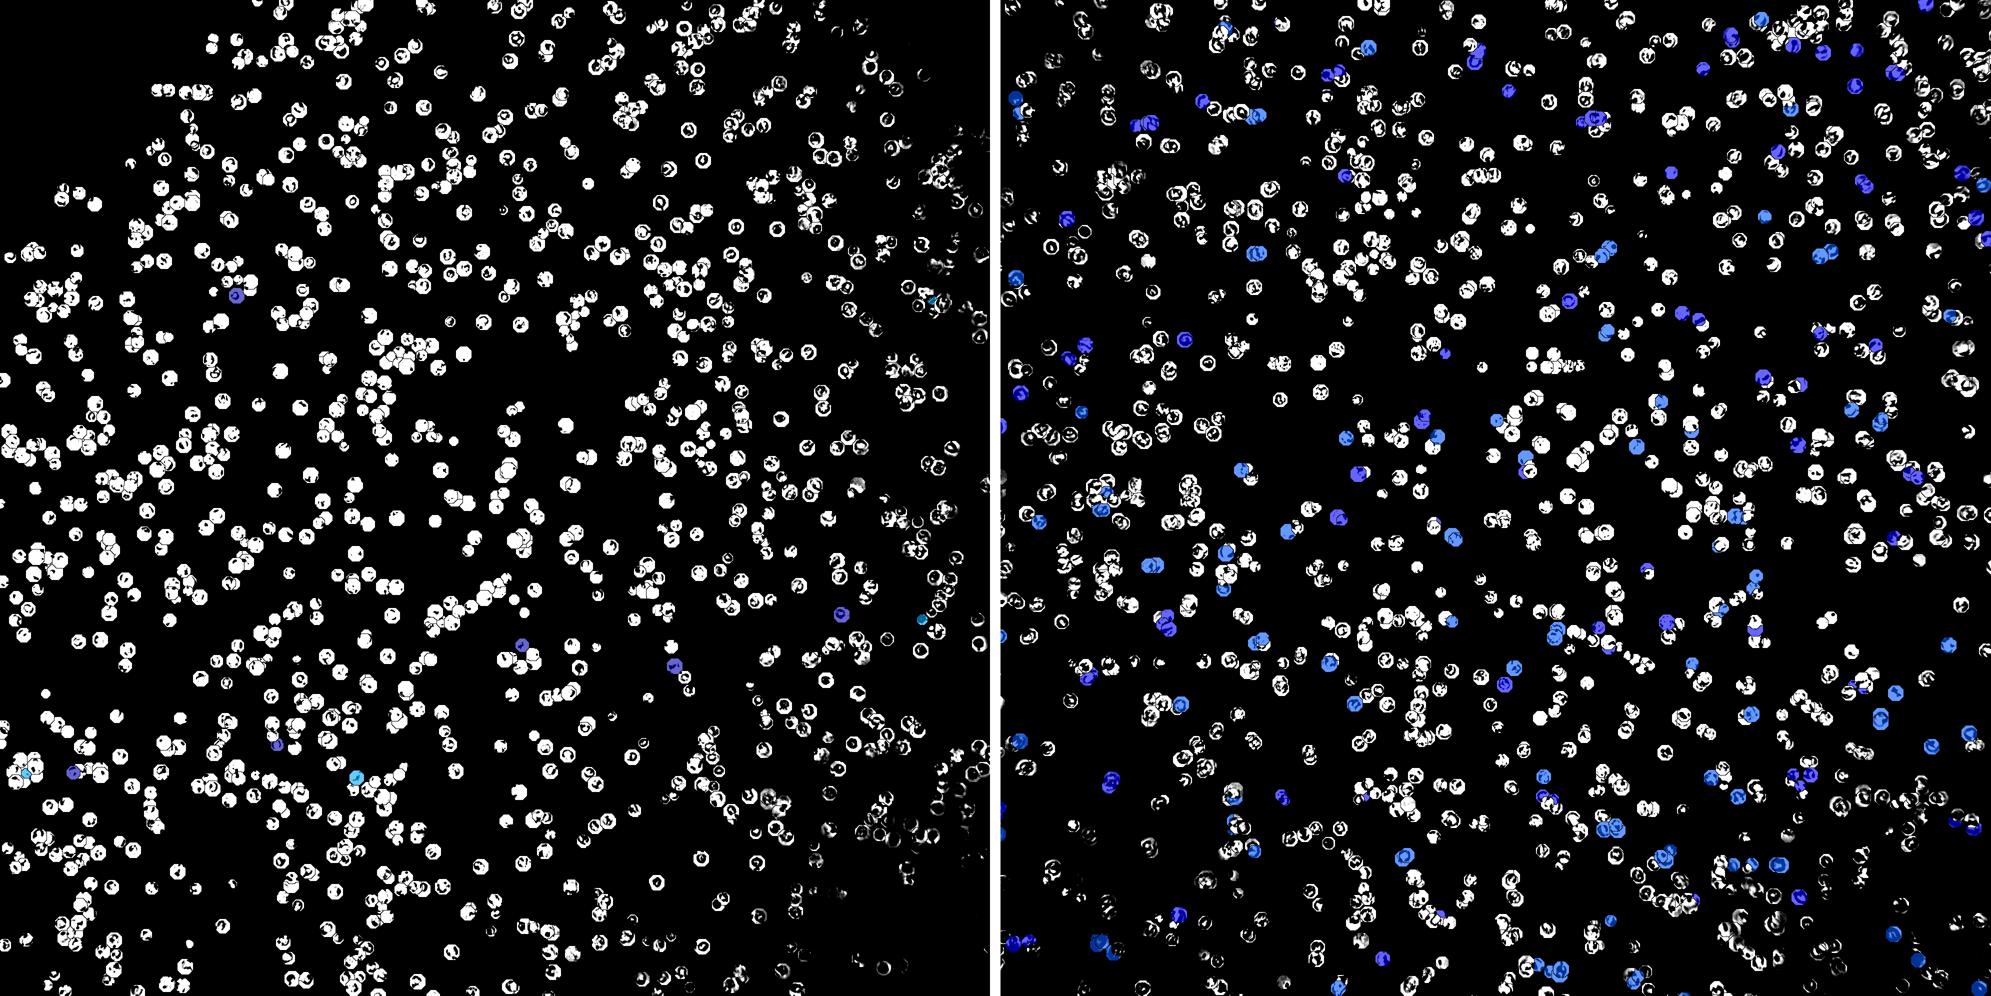

Cells labelled with CD24 CD8a

Cells labelled with CD24 TIA1

Peripheral blood lymphocytes

Inflammatory Disease

Cell populations before and after treatment